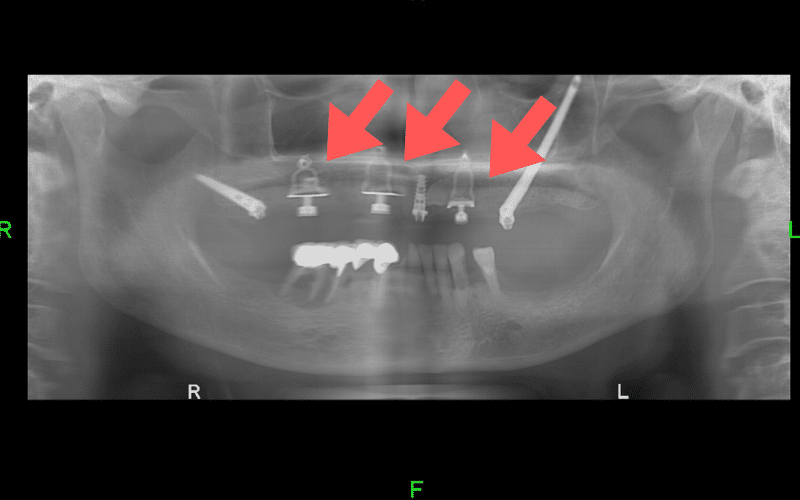

על מנת להבטיח את יציבותה של מערכת השיניים החדשה, שתלים בזאליים לעולם אינם יכולים לעמוד לבד אלא עליהם להיות משולבים עם שתלים דנטליים רגילים.

השתלים הרגילים יעוגנו באזורים שבהם עובי עצם הלסת מאפשר זאת (בדרך כלל בחלקים הקדמיים של הלסת), ואילו השתלים הבזאליים יחוברו באזורים שבהם עצם הלסת דלילה או שכבר אינה קיימת.

השתלה בזאלית משמשת פעמים רבות גם במקרים של חוסר עצם בלסת העליונה. במקרים כאלו שילוב של השתלים הבזאליים עם שתלים דנטליים רגילים ושתלי זיגומה ארוכים, מאפשר למטופלים להימנע מהצורך בסרבול הטיפול עם פרוצדורות כירורגיות ארוכות.